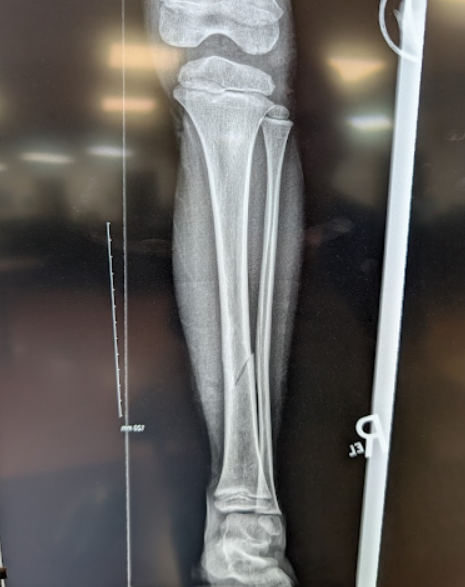

Small Jumps, Big Breaks

A previously healthy 7 year old male was downhill skiing and jumped off a ski feature, called a box, landing on his right leg. He developed immediate pain in his mid tibia and was unable to bear weight on his right leg. On arrival in the ED he has tenderness over the mid tibia with edema and ecchymosis. No tenderness over the ankle, knee, femur and no evidence of injury elsewhere. He is Neurovascularly intact distal to the injury. XRs of the tibia were done in the ED (Image 1).